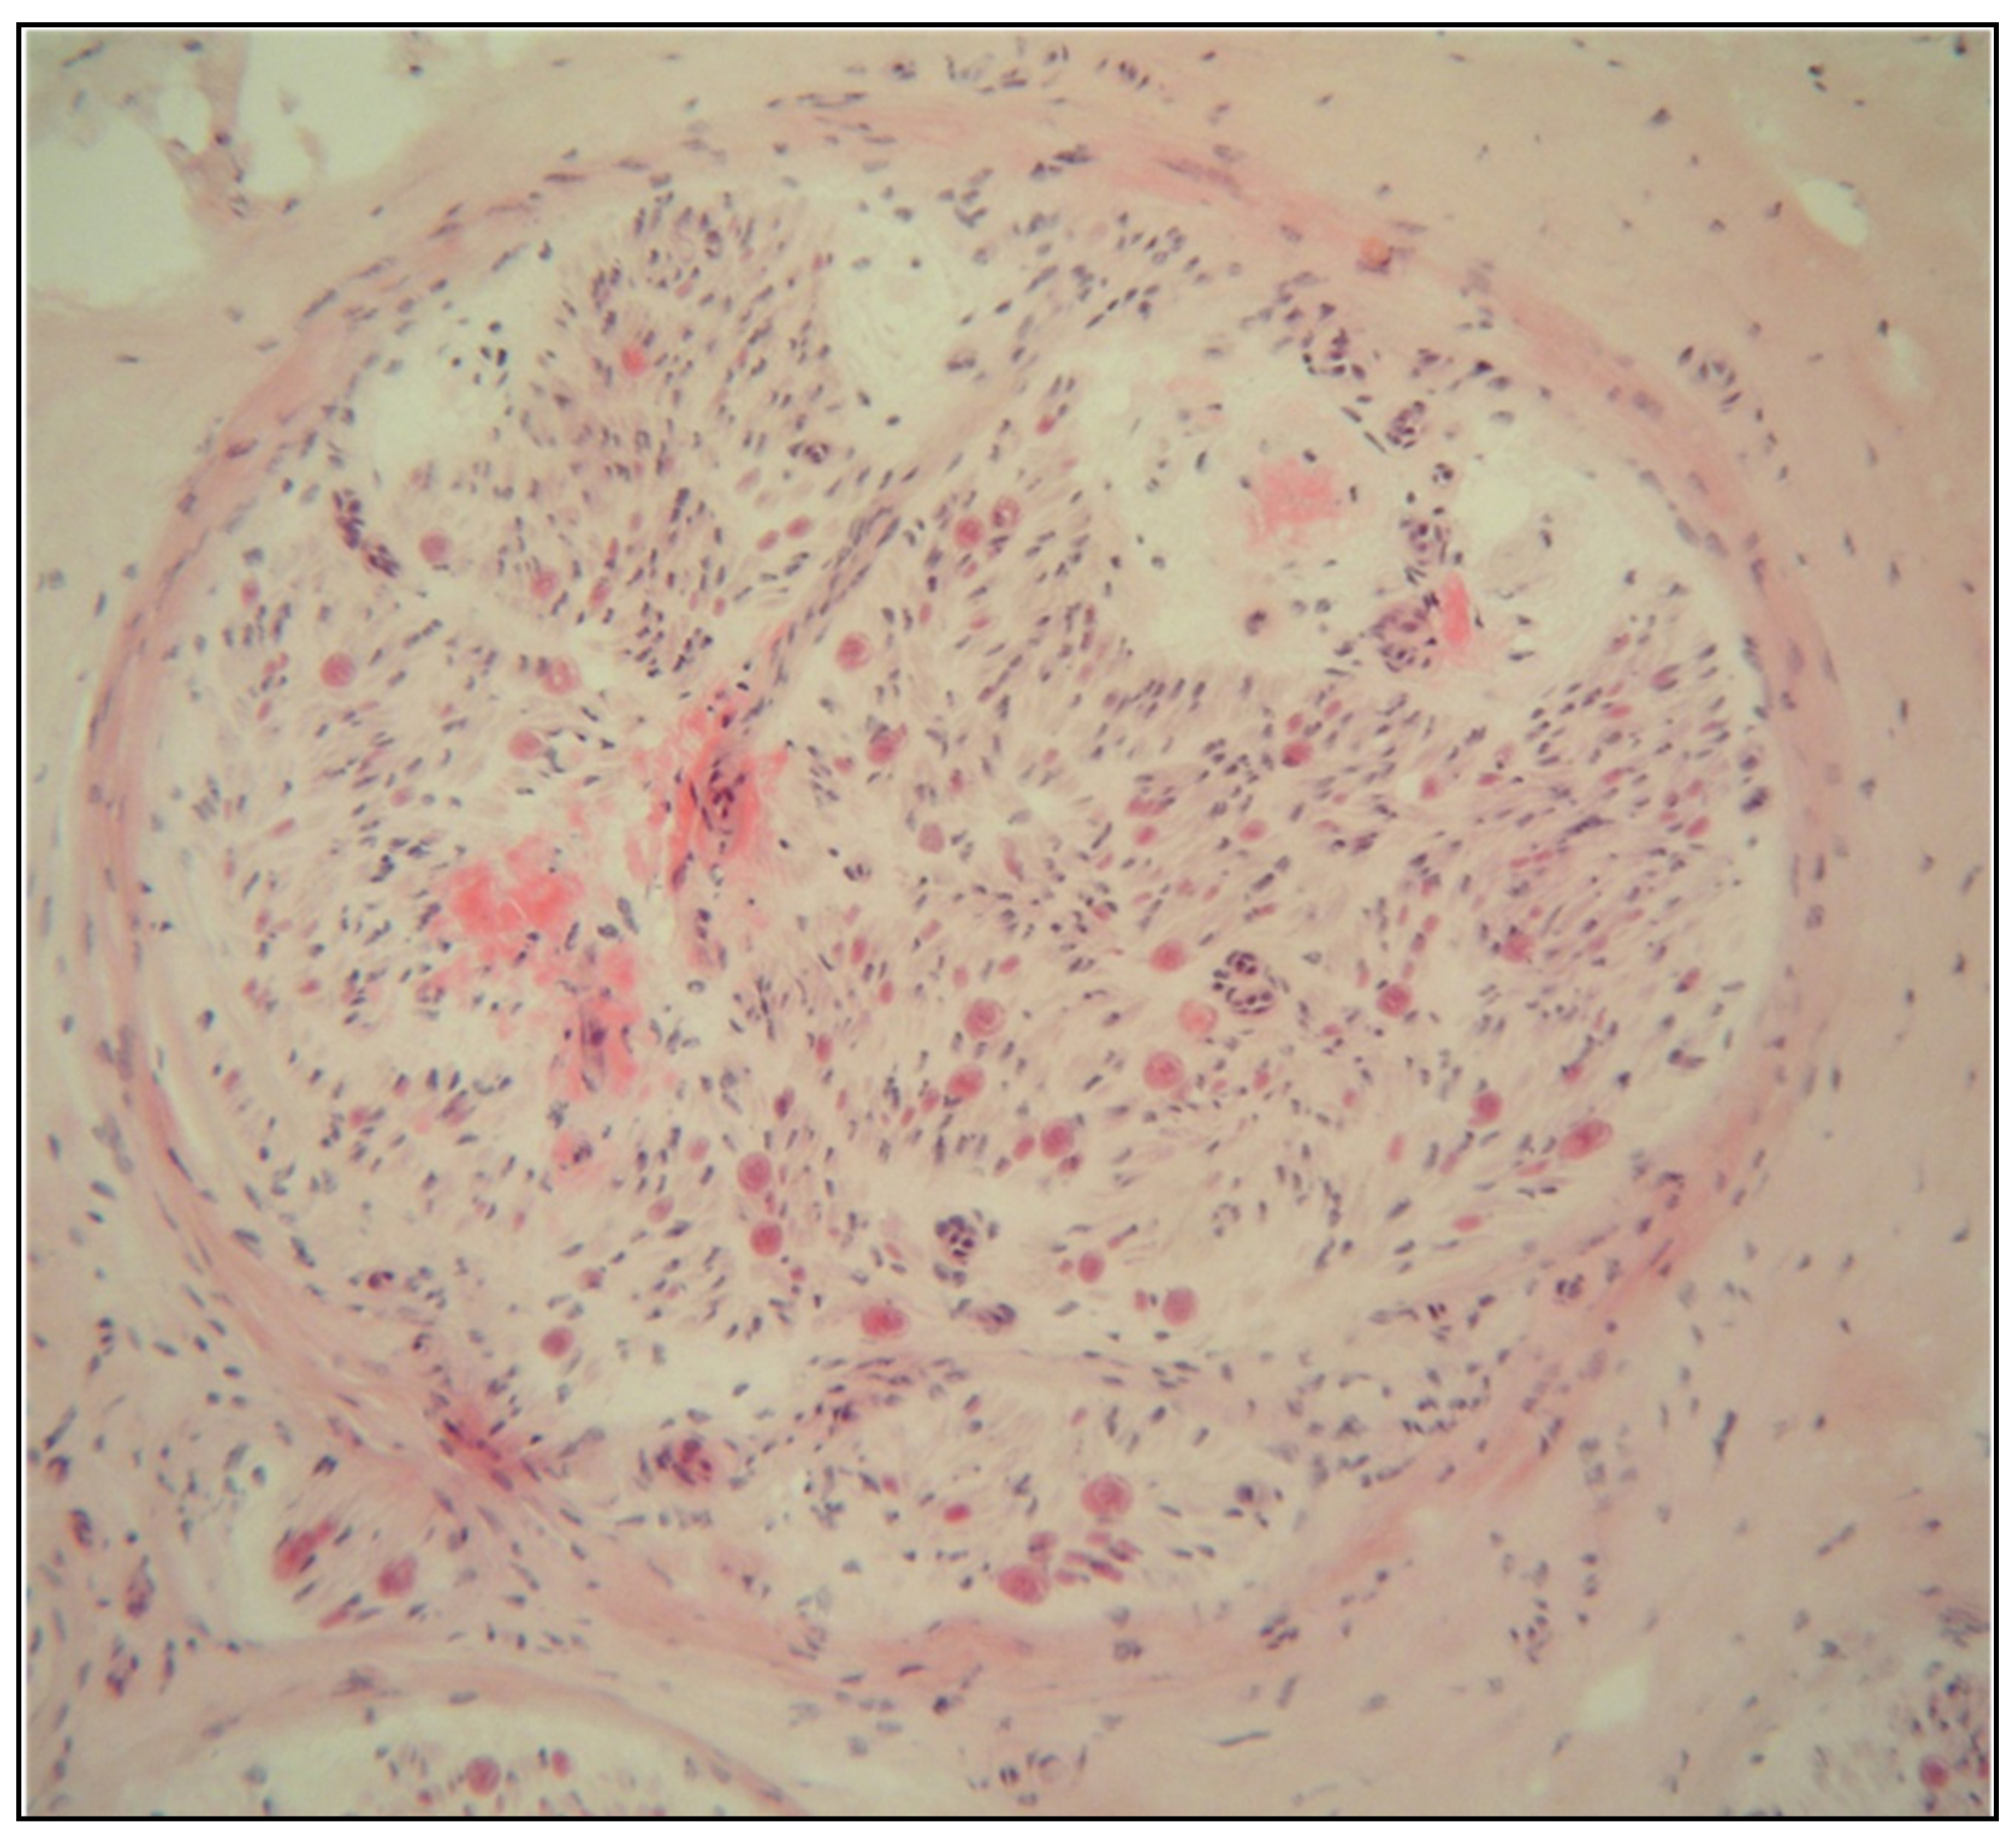

- Vitreous opacities